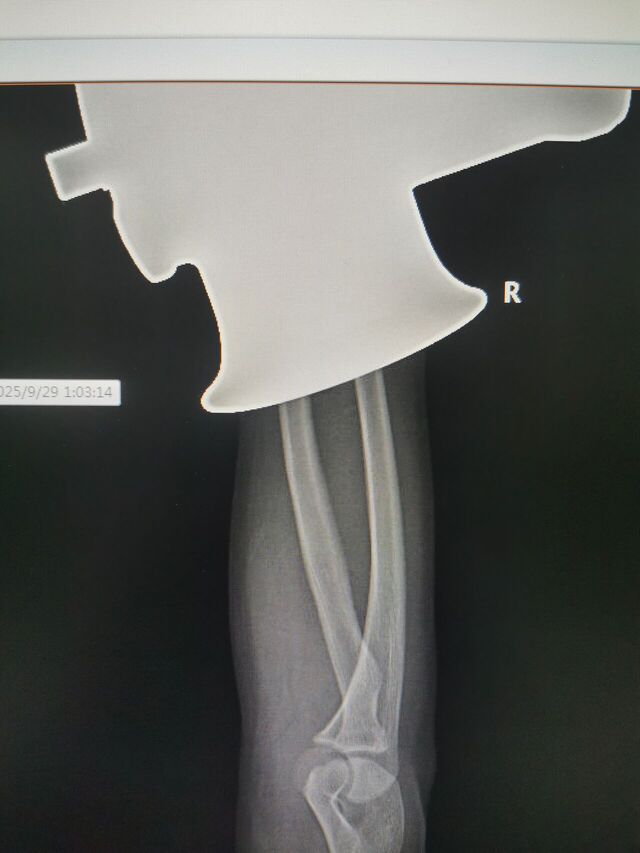

注定又是一个不眠夜!

等待119来破拆

16岁手进绞肉机了